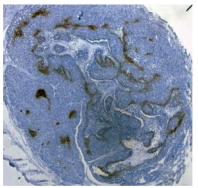

檢測(cè)原理:低氧標(biāo)志物測(cè)定是利用還原硝基有選擇性結(jié)合乏氧細(xì)胞的能力而形成的一種從細(xì)胞水平測(cè)定腫瘤乏氧的技術(shù),其原理是:腫瘤乏氧細(xì)胞還原能力強(qiáng),當(dāng)具有電子親合力的硝基咪唑主動(dòng)擴(kuò)散透過細(xì)胞脂膜,在細(xì)胞內(nèi)硝基還原酶作用下,硝基被還原,還原產(chǎn)物與大分子物質(zhì)不可逆結(jié)合,滯留在組織內(nèi)。而正常含氧細(xì)胞親電子硝基咪唑還原產(chǎn)物立即被氧化,從而用硝基咪唑類化合物在腫瘤內(nèi)的代謝程度來反映腫瘤的乏氧。

研究使用了Hypoxyprobe Inc品牌的Hypoxyprobe-1 Kit試劑盒(貨號(hào):HP2-100)來檢測(cè)脂肪組織中的缺氧狀態(tài)。